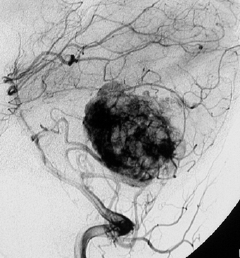

- 椎骨動脈撮影では,著明な腫瘍濃染像(血管がいっぱい)がみられて確定診断が可能です

左小脳にできた小さな のう胞性血管芽腫です。矢印の先にある小さな塊だけが腫瘍で周囲は腫瘍から染み出した液体が溜まっています(のう胞といいます)。右側は血管撮影とMRIを組み合わせた画像で,腫瘍に動脈が流入しているのが見えます。